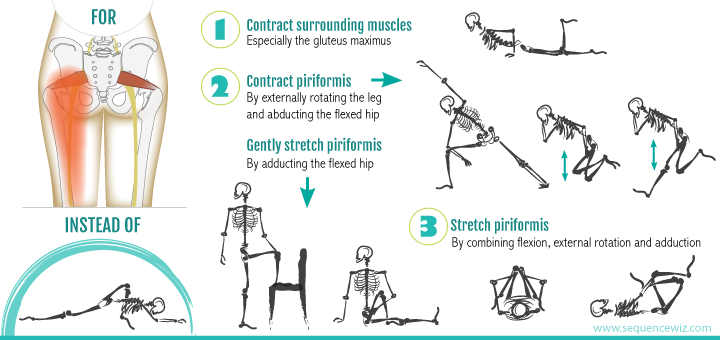

·原因: 疼痛大约在屁股摺痕处。尤其是在你膝盖伸直且将身体向前弯腰时,症状会更明显。这种型态的疼痛表示是连接到骨盆的腘绳肌肌腱受伤,这通常是因为过度的拉扯腘绳肌。(如在瑜伽中:当瑜伽练习者需要保持双腿笔直向前弯曲,然后强迫自己摆姿势时,可能最终会损伤肌腱。)当我们的肌腱受伤,腘绳肌会自然的收缩,试图去保护受伤的肌腱。然而我们认为的是:"腘绳肌紧绷又疼痛,要去伸展它,疼痛自然会消失了",而这样的方式却无法让肌腱修复,反而是重复使其受伤——过度伸展然后再受伤,这样的循环会使复原时间变更长。较好的方式是借由适当地收缩腘绳肌来增加受伤区域的循环,如果可以的话,做简单轻微的伸展。当疼痛急性期结束后,你可以慢慢增加伸展的角度。您的朋友或患者中,是否有人向你这样抱怨过:我的髋部在走路、睡觉时会痛,物理治疗师建议他作核心运动,骨科医师诊断他是梨状肌症候群,也试过请按摩师放松他紧绷的髂胫束。经过仔细的检查后,确认了他疼痛的位置,疼痛的症状都指向无力的外展肌群,造成骨盆位置不良,导致某些肌肉群去代偿。当开始训练他的外展肌群,很快地他的疼痛就不见了。此型态的疼痛通常会出现在臀部外侧或上侧,可能会向下至大腿的外侧。它通常是在散步跟晚上侧躺在患侧时更糟。薄弱的外展肌群,紧绷的髂胫束可能是引起疼痛的一种因素。这种疼痛常被认为是髂胫束的问题,所以借由伸展髂胫束,或用滚筒去放松,这会非常有效,但并没有解决问题的根源-外展肌无力,除非你去加强肌力,否则问题会一再出现。你需要锻炼你的髋外展肌,可以利用单脚站,另一侧大腿对抗重力做髋外展动作,两侧轮流施行,让髋外展肌做为稳定以及动作的功能角色。大家知道坐骨神经分布的范围到底有多大吗?它是你的身体里最长的一条神经,从下段脊椎一路延伸到脚,而且它也非常的粗,大概就像是你的小指头一样粗,穿过你的脊椎与髋关节。因为这条神经粗又长,它可能在很多地方被挤压到,而造成类似坐骨神经痛的症状。两个常见被挤压位置在下背部(腰椎椎体间)跟紧绷的梨状肌下面。梨状肌是一条很小的肌肉,当它太紧绷时可能会造成很多困扰。它位于髋部深处,在髋关节弯曲状态下,负责带动髋关节外转跟外展。紧绷的梨状肌会造成屁股痛,但当它压迫到通过梨状肌下面的坐骨神经时,就会使情况变得更糟。疼痛通常会出现在臀部中间的位置、下背部,或任何坐骨神经通过的地方。症状也有可能是脚麻或无力。如果是因为椎间盘突出引起的坐骨神经痛,是比较大的问题,超过我们本篇所要介绍的范围,在物理治疗师的指导下,加强核心肌群的运动是个不错的方式。如果疼痛是因为紧绷的梨状肌,我们可以着手于放松紧绷的肌肉。·较好的方式:利用我们常见的”收缩-放松-伸展原则”(Contract-Relax-Stretch principle)步骤①:从收缩周围肌肉开始(尤其是臀大肌),来增加此区域的血液循环。步骤②:然后我们可以轻轻的收缩梨状肌 (contract the piriformis ),让它慢慢放松掉原本慢性的收缩(如果不会感到疼痛),搭配温和的伸展。我们可以借鉴瑜伽中的动作,像是勇者式二(Virabhadrasana 2)、侧三角伸展式(Utthita Parsvakonasana)跟蚌蛤式都可以让梨状肌收缩,而在站姿下利用椅子做扭转动作,以及半鱼王式(Ardha Matsyendrasana)是伸展梨状肌最好的选择,因为此姿势会让你的脚处于弯曲、内收,但不会外转的姿势,这对于梨状肌是比较温和的姿势。步骤③:当你觉得你已经准备好在伸展加入外转的动作时,你可以选择穿针引线式(Thread-the-needle pose)来取代鸽式(Pigeon)或牛面式(Gomukasana),这会让使梨状肌受到较小的力矩。当你练习这些动作后,你就可以试着做鸽式(Pigeon)或牛面式(Gomukasana)。PS:但有些学生即使练习很久也还是没办法完成鸽式或牛面式。此外,由于过紧的内收肌群会使髋关节呈现内转姿势,使梨状肌产生额外的压力进而压迫到神经,所以也可使用相同的方式来舒缓内收肌群的慢性紧缩。紧绷的腘绳肌也会造成坐骨神经受压迫,所以对于缓解此肌群的张力也是很有效果的。请记住,即使最简易的腘绳肌伸展运动也可能造成一位有坐骨神经痛症状的人极大地疼痛,所以建议用前面提及到第一种臀部疼痛的腘绳肌伸展原则。 请记住,一个疼痛症状,有可能是许多原因造成的。如果您的疼痛在你经过一番努力后,仍然存在,应该是要去寻求专业建议的时候了。